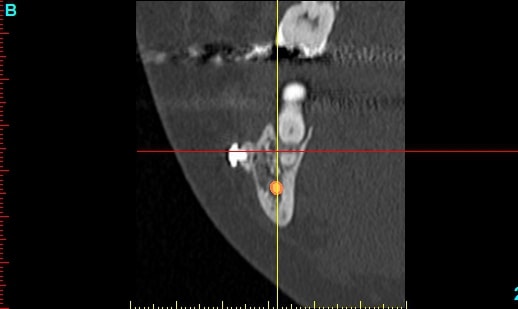

Patiente 58 ans à eu une chirurgie à visée esthétique et "fonctionnelle" adressée pour détartrage en urgence...je ne suis pas spécialiste mais je trouve que la greffe mentonnière est très bof

lésion apicale sur 42 risque de contamination sur la vis en regard..

j'ai demandé un scan en urgence.

Nous sommes d'accord pour la chirurgie mais secteur 4 il y a 2mm être là plastie et la mdble, ça ne me fais pas rêver

La chirurgie à 6 mois

Nous sommes d'accord pour la genioplastie je me suis mal exprimé ce qui m'inquiète c'est la proximité de la greffe, pardon genioplastie et de l'infection de 42, d'une part et la mauvaise liaison de la genioplastie secteur 4, mais je suis peut-être pessimiste.

N'ayant aucune donnée j'essaie d'abord de faire le tri,avant de mettre les mains dedans...je raisonne comme en implanto, quand il y a un foyer infectieux à distance proche (42) je pense qu'il y a un risque...

Plusieurs points: les vis de 15mm x 2mm qui transfixent c'est pas top, une seule plaque, qui plus est non réglable de chaque côté, c'est encore moins top. C'est une plaque de fracture.

En mandibulaire gauche c'est quoi ce fil d'osteosynthese? Un troisième fragment? En laissant l'apex de la 48 pile sur le trait d'osteotomie, je dis chapeau.

Pour la lésion de 42, ca peut être lié à la genio. Forage hasardeux? Mais je vote plus pour une lésion endo/paro